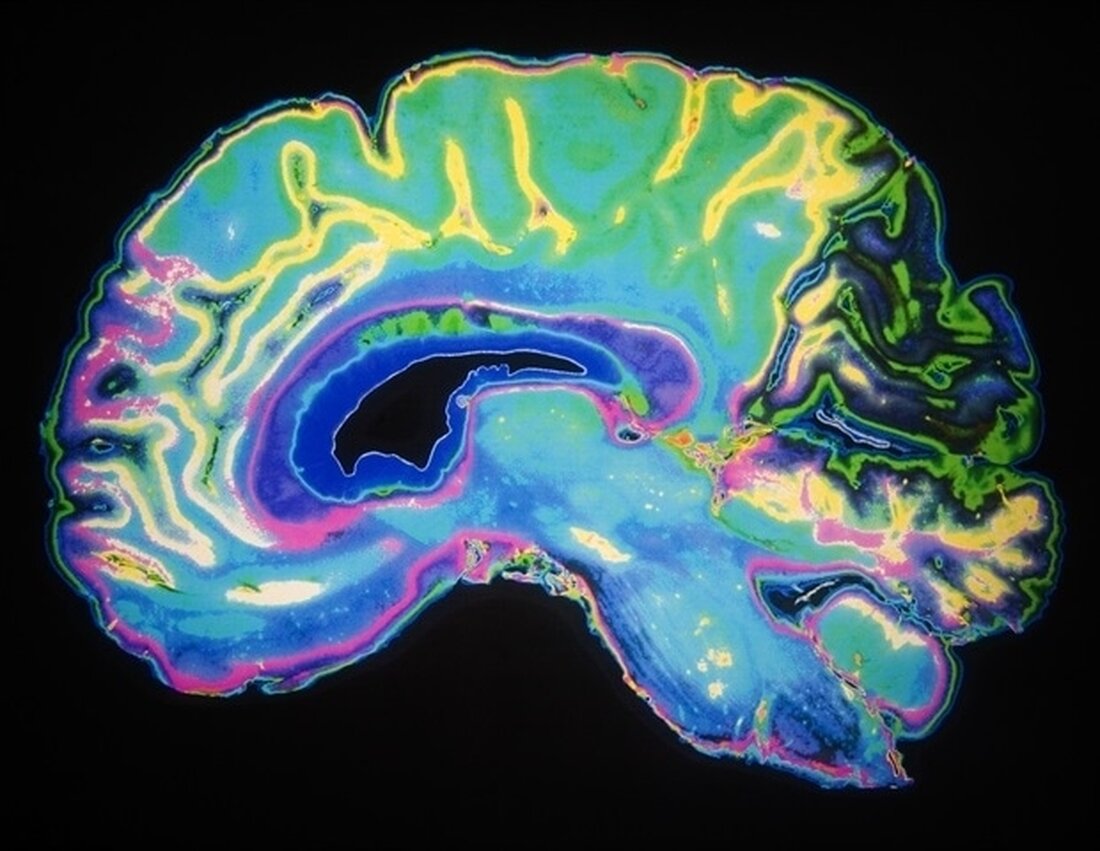

In einer kürzlich in Neuropsychopharmacology veröffentlichten neuen Studie hat ein Team unter der Leitung von Forschern des McLean Hospital, der größten psychiatrischen Tochtergesellschaft der Harvard Medical School und Mitglied von Mass General Brigham, Regionen innerhalb von Gehirnnetzwerken identifiziert, die miteinander kommunizieren, wenn Menschen unterschiedliche Typen erleben von dissoziativen Symptomen.

Die Studie von Lebois und ihren Kollegen umfasste 91 Frauen mit und ohne Vorgeschichte von Kindheitstraumata, aktueller posttraumatischer Belastungsstörung und mit unterschiedlichen dissoziativen Symptomen. Die Teilnehmer absolvierten einen funktionellen Magnetresonanztomographie-Scan, damit die Forscher Einblick in ihre Gehirnaktivität gewinnen konnten.

„Die neuartigen Methoden, die wir zur Untersuchung der Gehirnkonnektivität verwendet haben, sind entscheidend für das Verständnis der Rolle, die diese Netzwerkstörungen bei dissoziativen Störungen spielen“, sagte Co-Seniorautorin Lisa D. Nickerson, PhD, Direktorin des Applied Neuroimaging Statistics Lab am McLean Hospital.

Die Wissenschaftler fanden heraus, dass verschiedene dissoziative Symptome eindeutig mit Verbindungen von Bereichen in Gehirnnetzwerken assoziiert sind, die für Kognitions- und Emotionsprozesse verantwortlich sind. „Wir fanden heraus, dass Dissoziation, die für posttraumatische Belastungsstörungen typisch ist, und Dissoziation, die für DIS zentral ist, jeweils mit einzigartigen Gehirnsignaturen verbunden sind“, sagte Lebois.